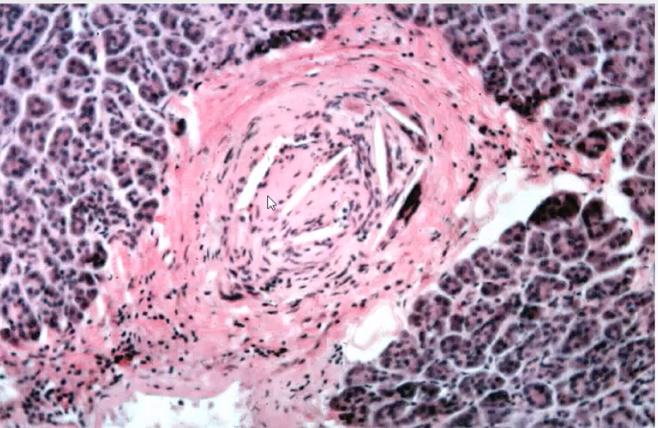

This is something that can be seen in the test and it is important to know that these kind of lesions are not a plaque progression problems but embolism problem and can be a marker for aortic embolism

These are not cholestrol clefts but this is Recanalization where after oclusion of the vessel small vessels form within the artery to deliver blood, these vessels form by angiogenesis